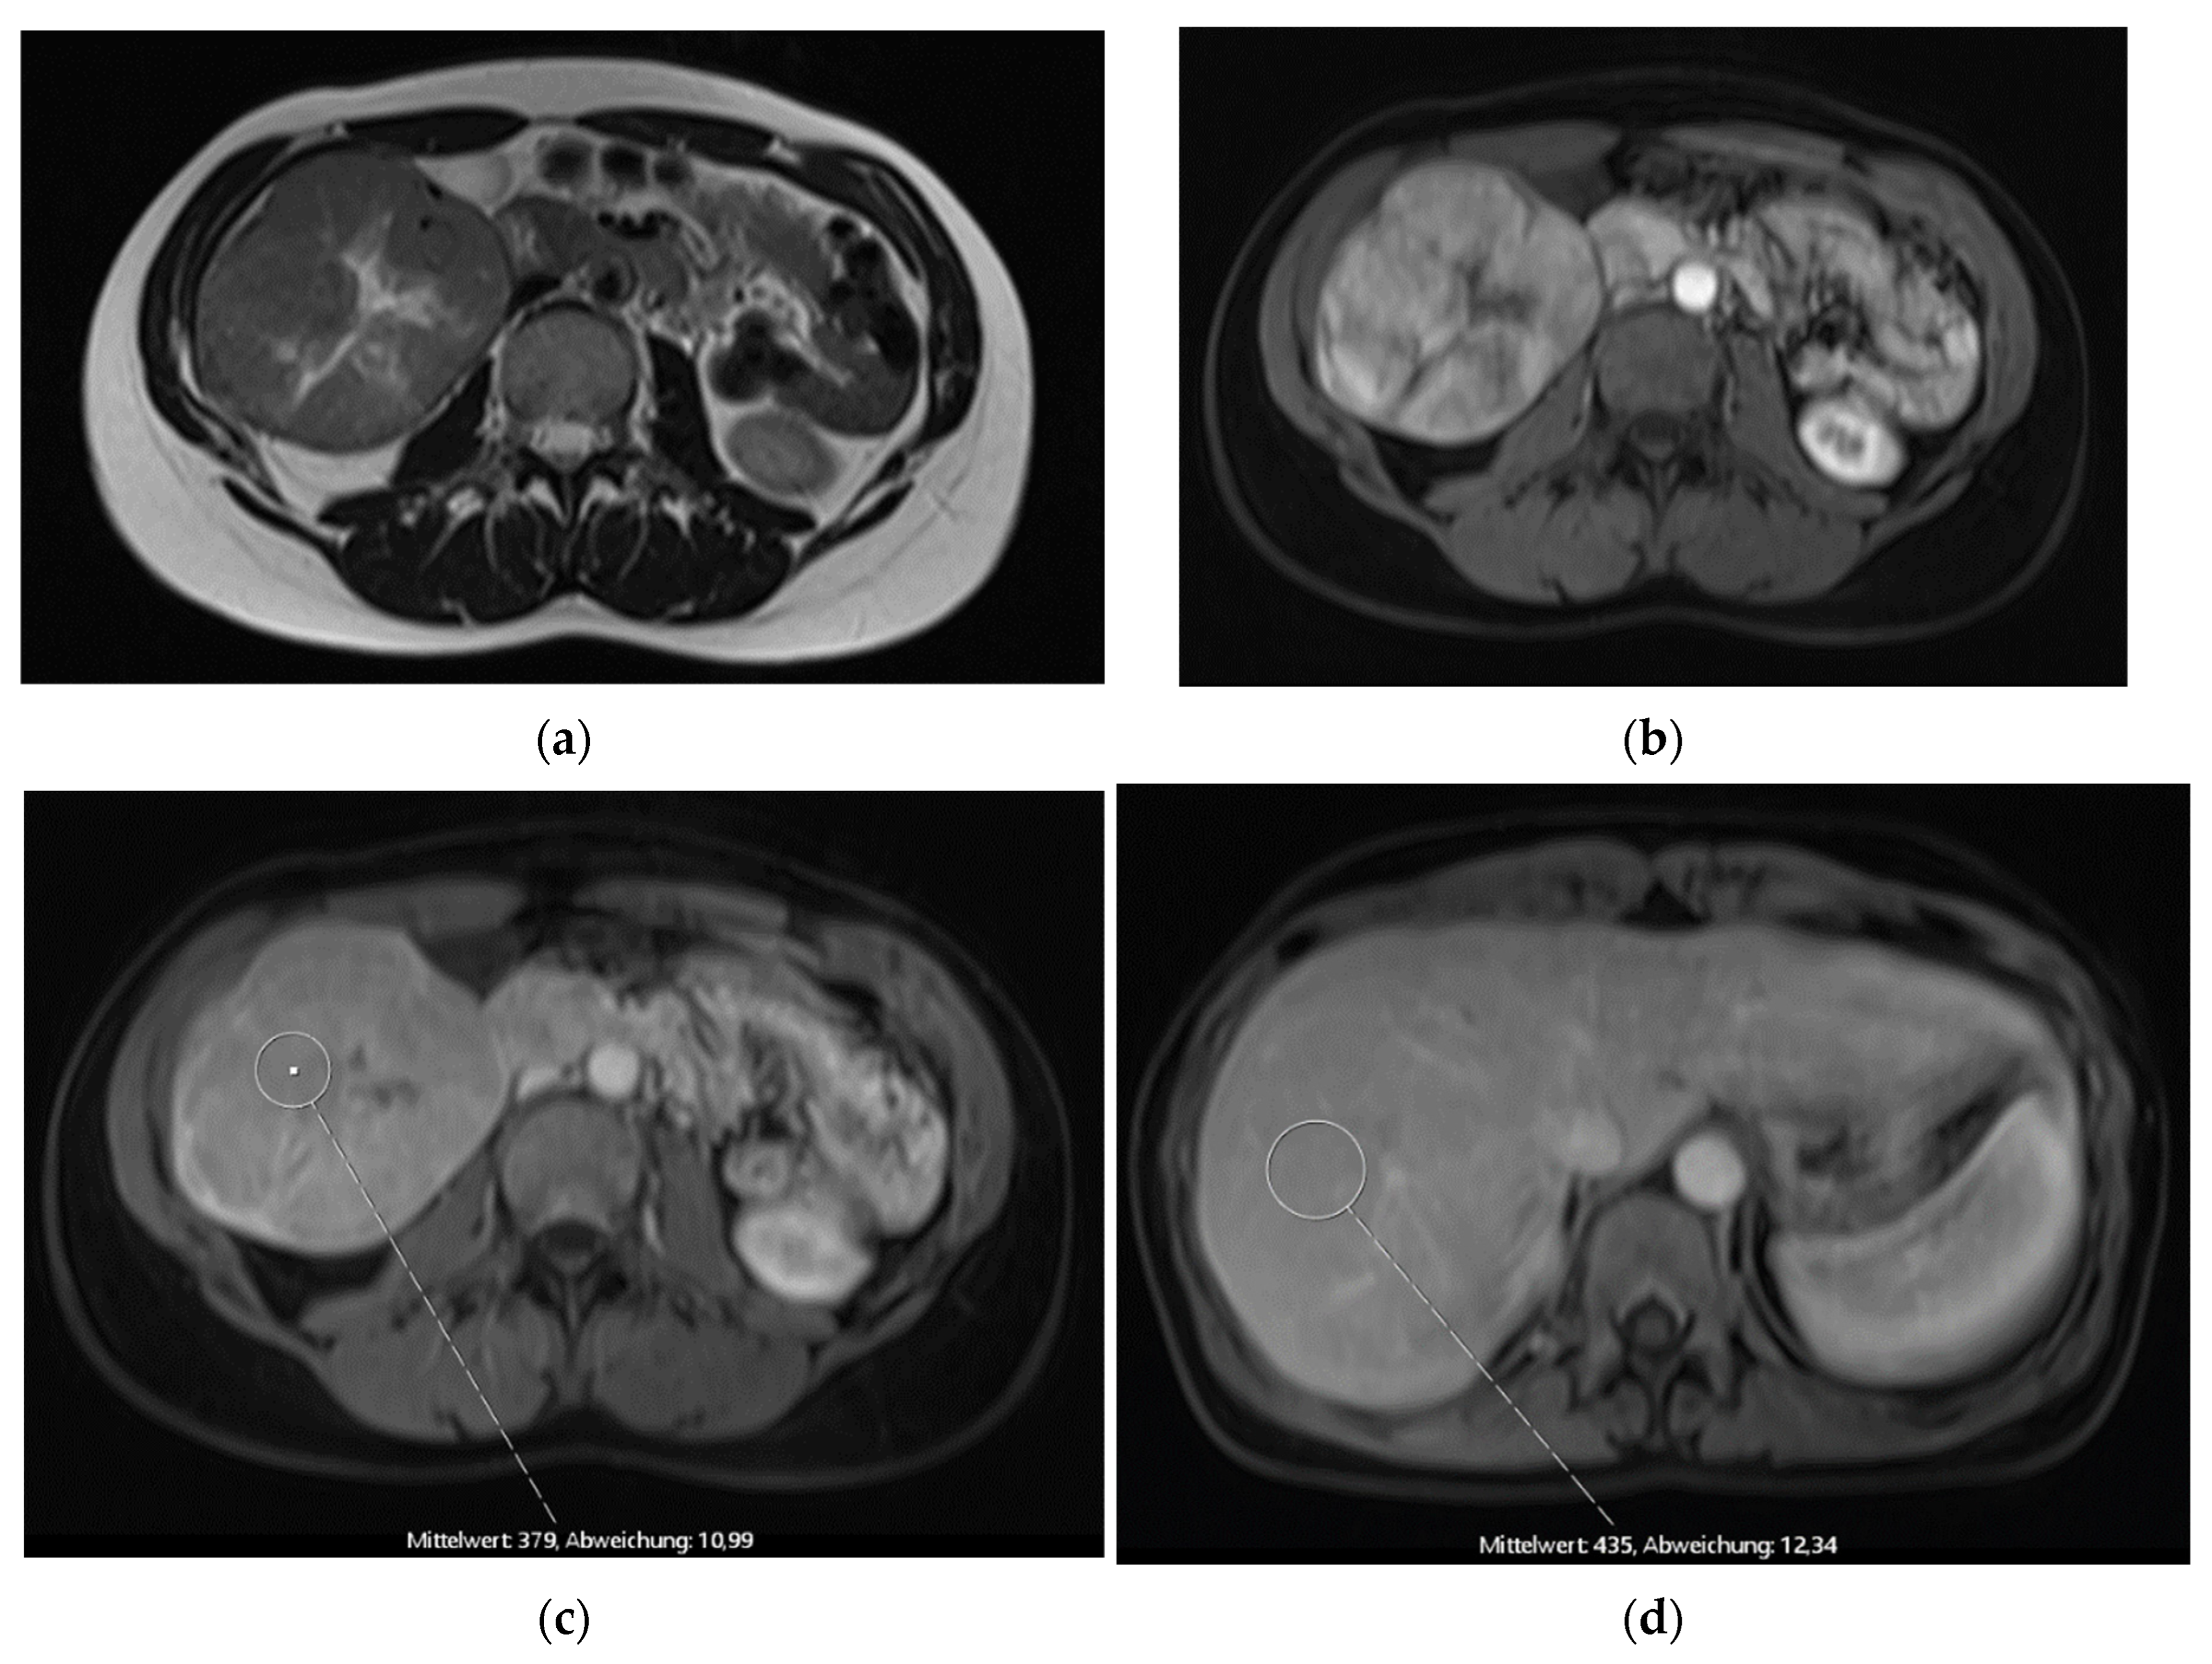

Figure 3. Pre-operative MR imaging Patient 3: (a) T2 TSE sequence depicting central scar; (b) T1 sequence with fat saturation in depicting intense early arterial enhancement; (c) Late venous phase imaging showing iso-/hyperintensity of solid components to healthy liver tissue.

The third patient was 53 years old when a FNH was diagnosed in MRI (Figure 3). Comparable to patient 1, no dedicated delayed hepatobiliary phase had been was performed. A follow-up after 3 months was scheduled, this time with Alpha-1 Fetoprotein (AFP) as laboratory testing, which turned out to be significantly increased with a value of > 400000ng/ml. At presentation at our center four weeks later the AFP had risen to 980,128 ng/ml. We conducted a central resection of segments 4, partially 5 and 8 as well as Segment 1 (H145′8′-RHV). Resection and reconstruction of the right hepatic vein was necessary to achieve R0-status. The patient is tumor-free within follow-up for 20 months until today. In the postoperative course the AFP levels decreased to 5529 ng/ml after one month, to 4.9 ng/ml after three months, and remained below 2.5 ng/ml since seven months after resection.